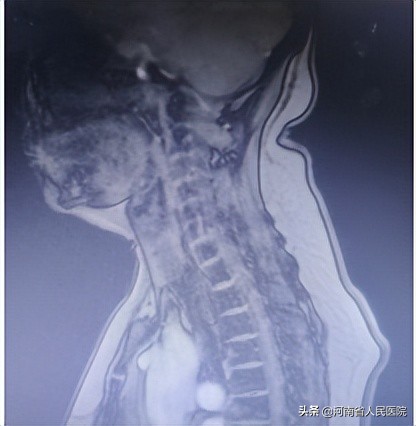

富贵包,也称为贵妇包,是位于颈部后侧下方区域的一个大包。在后背上部颈胸交界处,即第七颈椎和第一胸椎处,因为体力劳动或是长时间从事低头负重工作的人导致颈部凸出的硬包块,也称为颈部部分后凸畸形。

它的临床表现为脂肪堆积,除了严重影响个人形体的美观,富贵包还经常伴随着颈部疼痛、头晕头疼和肌肉痉挛等健康问题。导致人的上背部驼背、僵硬或背痛、平衡感不好,容易导致摔倒、腿部肌肉绷紧 、胸肌紧绷、不良的代偿姿势,由于脊柱弯曲,严重的还可能导致呼吸困难。